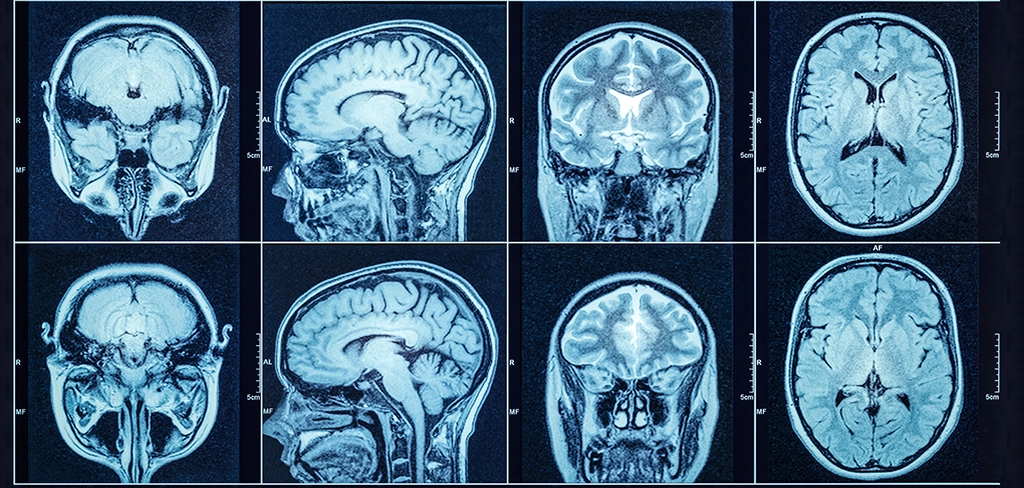

Комп’ютерна томографія (КТ) голови – це сучасний метод діагностики, що дозволяє отримати точні зображення структур головного мозку, черепа, орбіт та навколоносових пазух. Завдяки високій роздільній здатності, КТ допомагає швидко виявляти патології та пошкодження, особливо в ургентних ситуаціях, де кожна хвилина є вирішальною. Метод є інформативним при діагностиці травм, інсультів, новоутворень та запальних процесів, що робить його незамінним у невідкладній медицині та нейрохірургії.

Комп'ютерна томографія голови дозволяє отримати чітке зображення різних структур голови, що робить її незамінною для швидкої діагностики в невідкладних ситуаціях. Завдяки цьому методу лікарі можуть точно визначити патології і обрати оптимальний план лікування, що сприяє швидкому відновленню пацієнта. Метою обстеження може бути безпосередньо паренхіма головного мозку, артерії або судини головного мозку, кістки черепа і ЛОР-органів. Також досліджується щелепно-лицева зона, а в деяких випадках – структури основи черепа та шийний відділ повністю або частково. Щоразу протокол сканування вибирається під клінічну задачу, яку ставить лікар-клініцист.

Комп'ютерна томографія (КТ) голови та мозку має ряд особливостей, які роблять її важливим діагностичним інструментом у неврології, нейрохірургії та невідкладній медицині. Вона дозволяє отримувати високоточні зображення кісткових і м'якотканинних структур, що дає можливість своєчасно виявляти та оцінювати пошкодження чи патології. Складність сканування головного мозку полягає в тому, що мозок знаходиться у черепній коробці, кістки черепа досить щільні, особливо в області основи черепа, а сам мозок – нещільна слабоконтрастна структура. Відповідно, для того щоб отримати хороше інформативне зображення паренхіми мозку при обстеженні, рентгенівський промінь має пробити кісткові структури й забезпечити достатньо чітке зображення слабоконтрастних структур. Тому для оцінки головного мозку потрібні спеціальні параметри сканування. Основні особливості КТ голови та мозку:

Після цього проводиться реконструкція зображень з різною товщиною зрізу. Це можливо виконати лише при скануванні на мультидетекторних комп'ютерних томографах. Товстіші зрізи потрібні для швидкої оцінки речовини мозку, тонкі – для побудови мультипланарних реконструкцій, а тонкі зрізи з жорстким Кернеллом необхідні для оцінки кісткових структур основи черепа, скроневих кісток і склепіння черепа.

Комп'ютерна томографія (КТ) головного мозку – це один із найважливіших методів діагностики захворювань і травм, який дозволяє отримати пошарові зображення мозкових структур з високою точністю. Цей метод застосовується для оцінки стану мозку при гострих станах, таких як інсульт або черепно-мозкова травма, а також для планових досліджень з метою виявлення новоутворень, аномалій розвитку чи запальних процесів. Частково це можуть бути ургентні випадки, що потребують негайної госпіталізації, наприклад, при різних крововиливах, інсультах, ішемічних інфарктах або розривах аневризм.